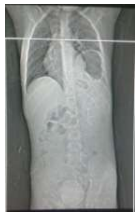

RN em sala de parto apresentou desconforto respiratório e foi encaminhado para UTI neonatal. Na admissão apresentava desconforto respiratório, cianose discreta e SO2 90%. Fez RX de tórax com o seguinte achado radiológico:

Diante deste achado, assinale a alternativa que indica o diagnóstico e a melhor conduta.